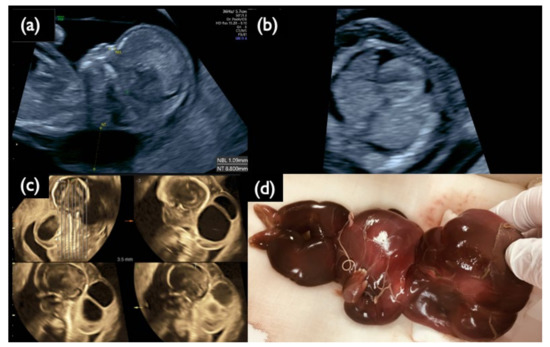

| FP1 | 45,X | T21 positive | 3.55 | MX+ T21 (16%) | MX+D21 | MX+ T21 (8%) | MX+D21 | – | – | MX+ T21 (4%) | 46,XX | CPM | + | 8.8 | Increased NT, CH, General edema, PE bilateral, Small NB, Tachycardia, Short FL/HL, Turner is strongly suspected | |

| FP2 | 46,XX | T21 positive | 4.18 | D21 | D21 | D21 | D21 | D21 | D21 | D21 | D21 | 46,XX | s/o nonviable twin with T21 | – | 2.2 | TR mild, DCDA vanishing twin with a nonviable fetus |

| FP3 | 46,XY | T21 positive | 7.52 | D21 | D21 | D21 | D21 | D21 | D21 | D21 | T21 (14–74%) * | 46,XX | nonviable twin with T21 | – | 1.4 | Small NB, TR mild, DCDA vanishing twin with a nonviable fetus |

| FP4 | 46,XY | T21 positive | 7.78 | D21 | D21 | D21 | D21 | T21 (15%) | D21 | D21 | D21 | 46,XX | CPM | – | 2.2 | Small NB, TR mild |